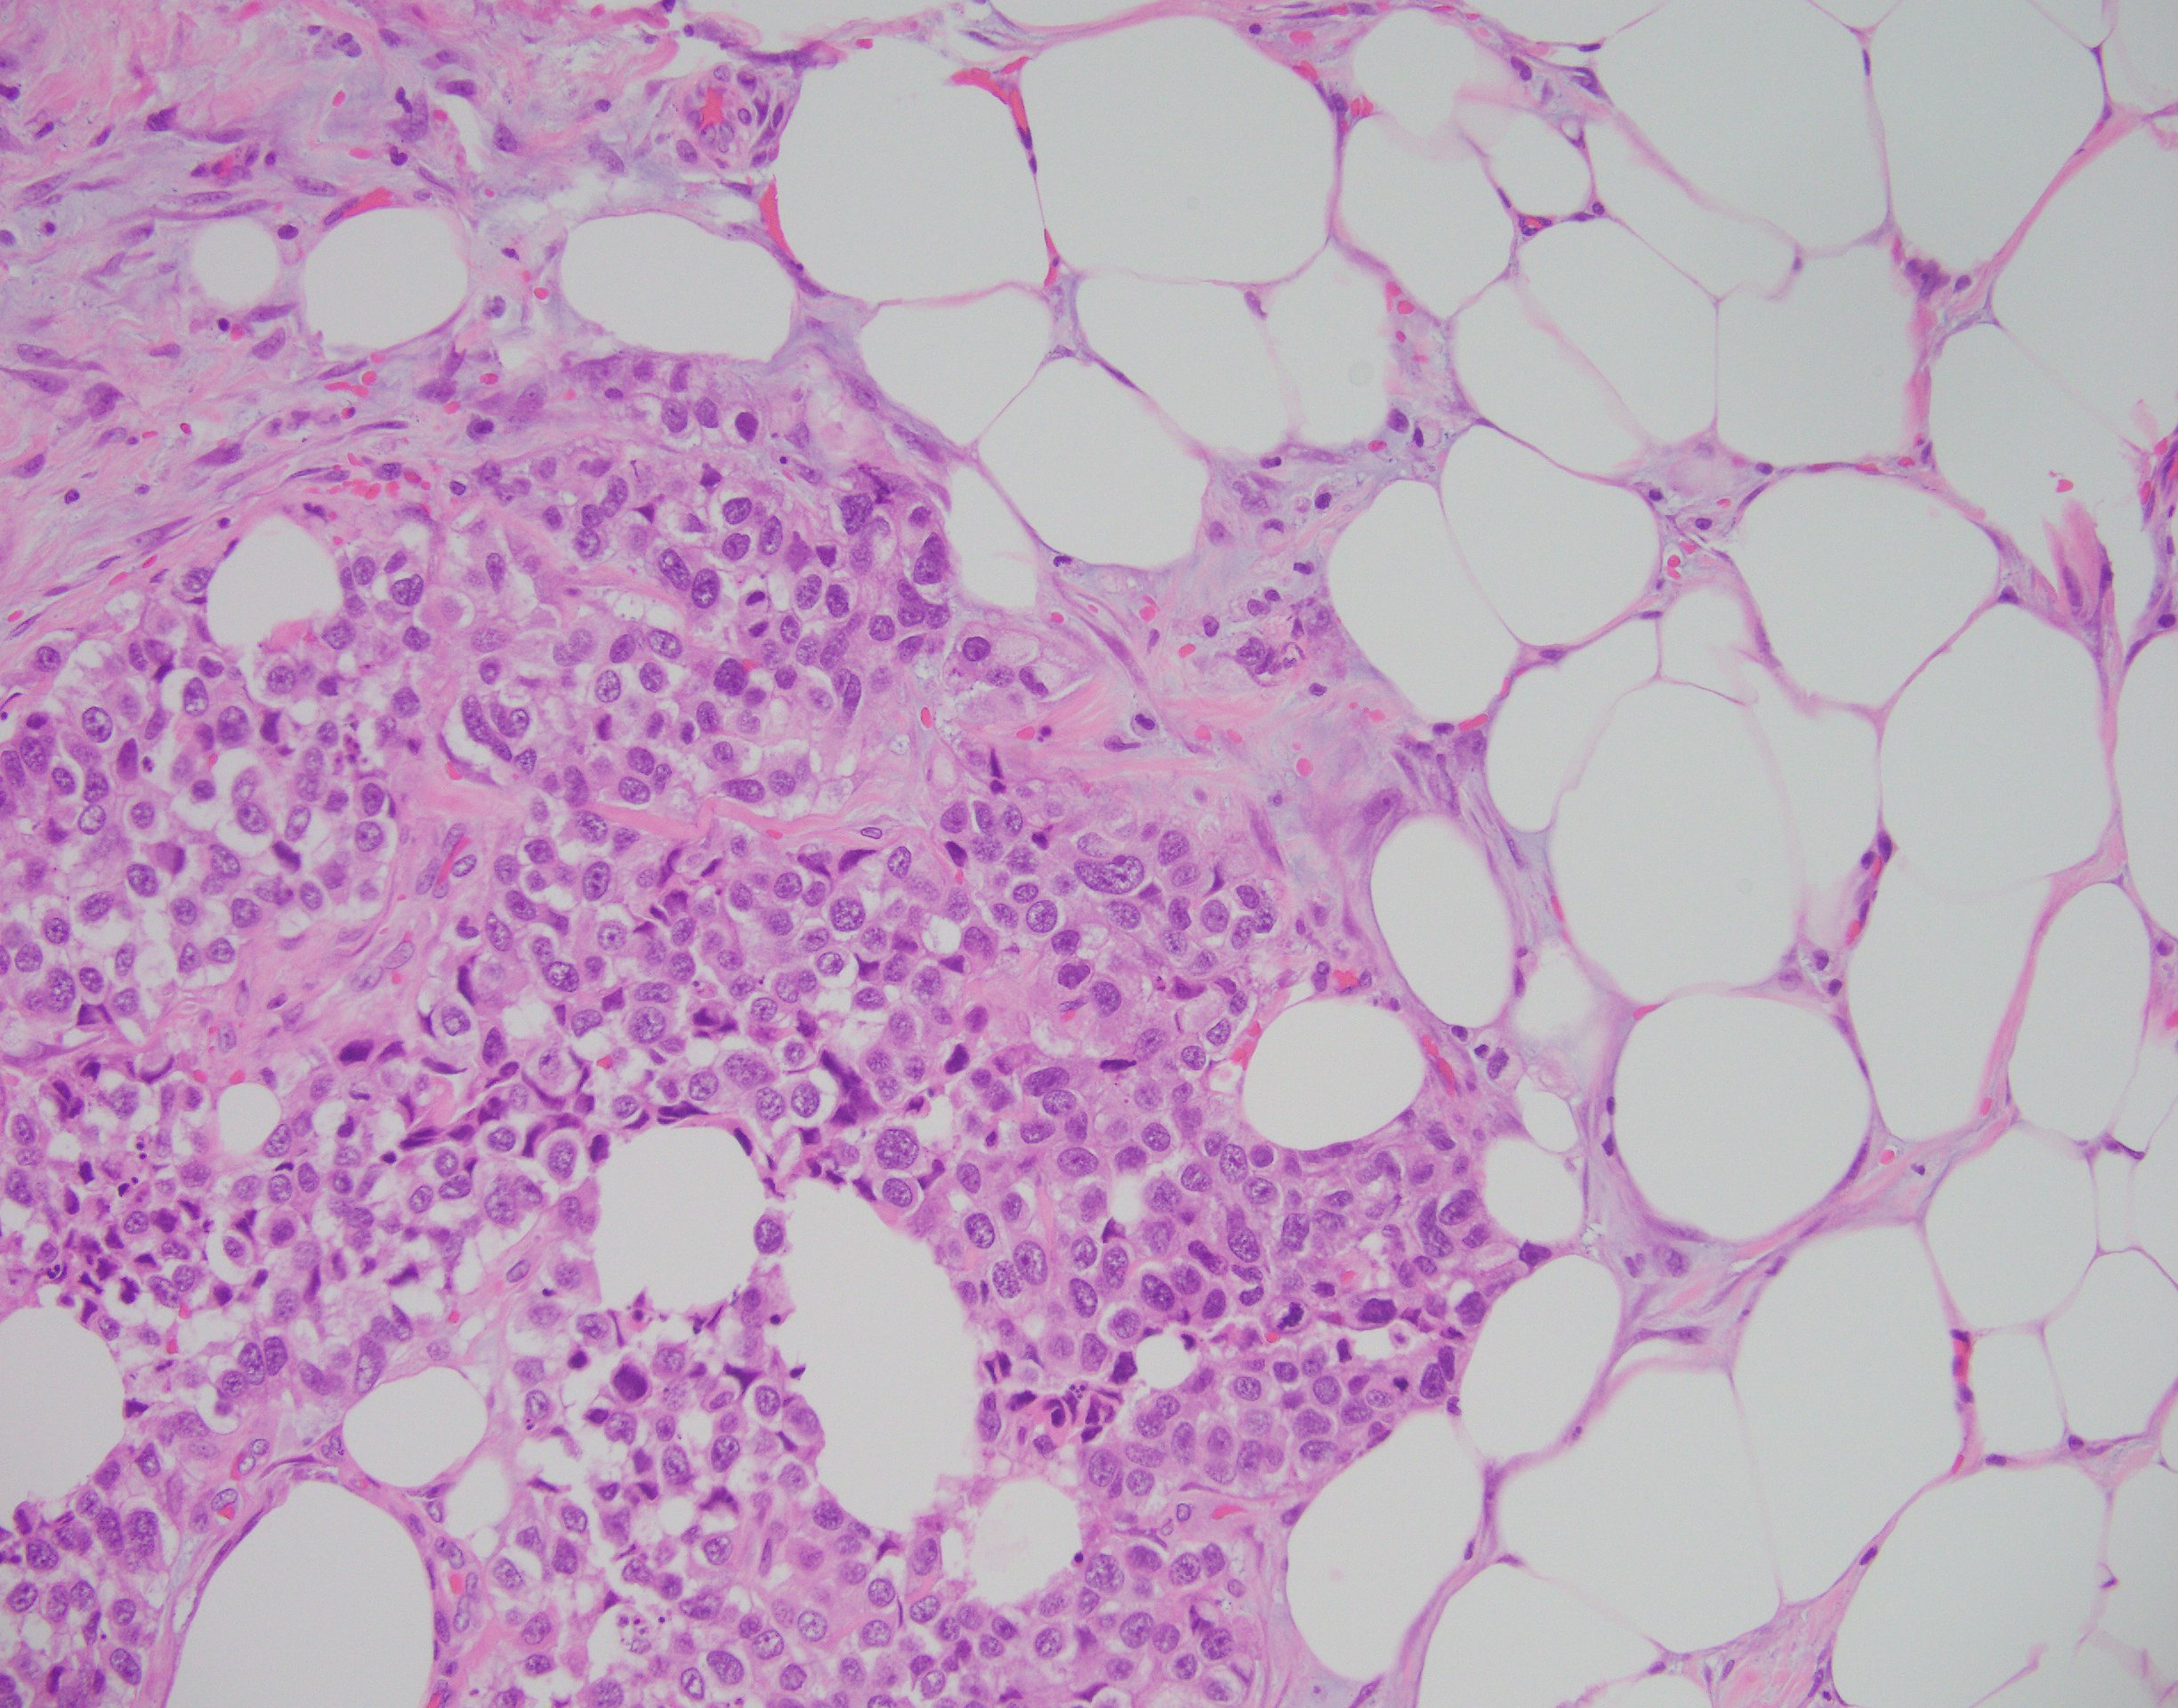

The findings in this case show a diffuse, infiltrative, and discohesive tumor extending into the perivesical adipose tissue. There is extensive perineural and lymphovascular invasion. Focal areas show urothelial carcinoma in situ. Tumor cells have eosinophilic cytoplasm, and nuclei are eccentrically located with focal signet ring cell features. Staining with p63 and GATA3 was performed and shows positivity in both stains.

These features are all consistent with the plasmacytoid variant of urothelial carcinoma. Typically, this variant grows in a linitis plastica-like manner. Tumor infiltration is diffuse, in single cells or cords. Characteristically, tumor cells exhibit eccentric nuclei and/or signet ring cell morphology. Of note, these tumors stain similar to usual urothelial carcinomas, but also strongly express CD138 and lose E-cadherin expression. Most tumors are locally advanced at the time of diagnosis and are highly aggressive.